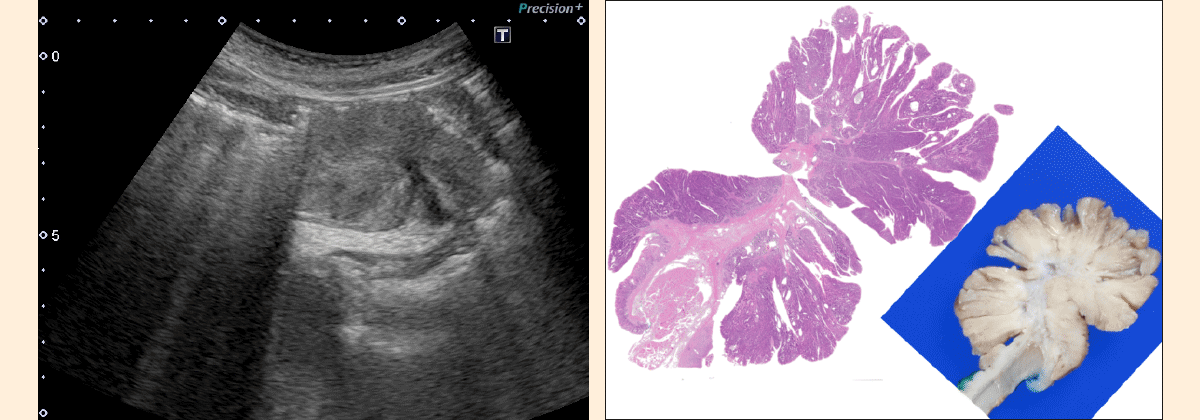

胃体下部に腫瘤が見られた症例.超音波像の所見から深達度を固有筋層(MP)までと判断したが,病理組織像を見ると,癌は粘膜内に留まっていた.

市 原:病理を見た時に,有茎性病変が「ポイツ・イェガース型ポリープ(Peutz-Jeghers type polyp)に似ている場合」には,深達度は基本的に浅いだろうな,と感じます.少し古い症例ですが,参考症例をお持ちしました(図1).ポイツは癌や腺腫ではなく,過形成に近い病変ですので,粘膜下層以深には浸潤しません.しかし,固有筋層の巻き込みが激しく,粘膜切除では病変を採ることができませんでした.腸閉塞症状があったため,手術になった方です.

図1 小腸 Peutz-Jeghers type polyp

網かけ部:固有筋層(MP),青塗りつぶし部:粘膜下層(SM)の線維化,黄矢印:太い血管.

有症状のため腸管切除された症例.固有筋層が引き込まれている.非腫瘍性病変であり,浸潤はみられない.

市 原:そうなんです.「分葉状の隆起で,筋肉が牽引されるくらい上方に盛り上がっており,中心部に木の幹のように枝分かれする芯が通っていて,そこには血管が走行している」病変です.癌ではないため浸潤はないのに,固有筋層がしっかり引き込まれています.